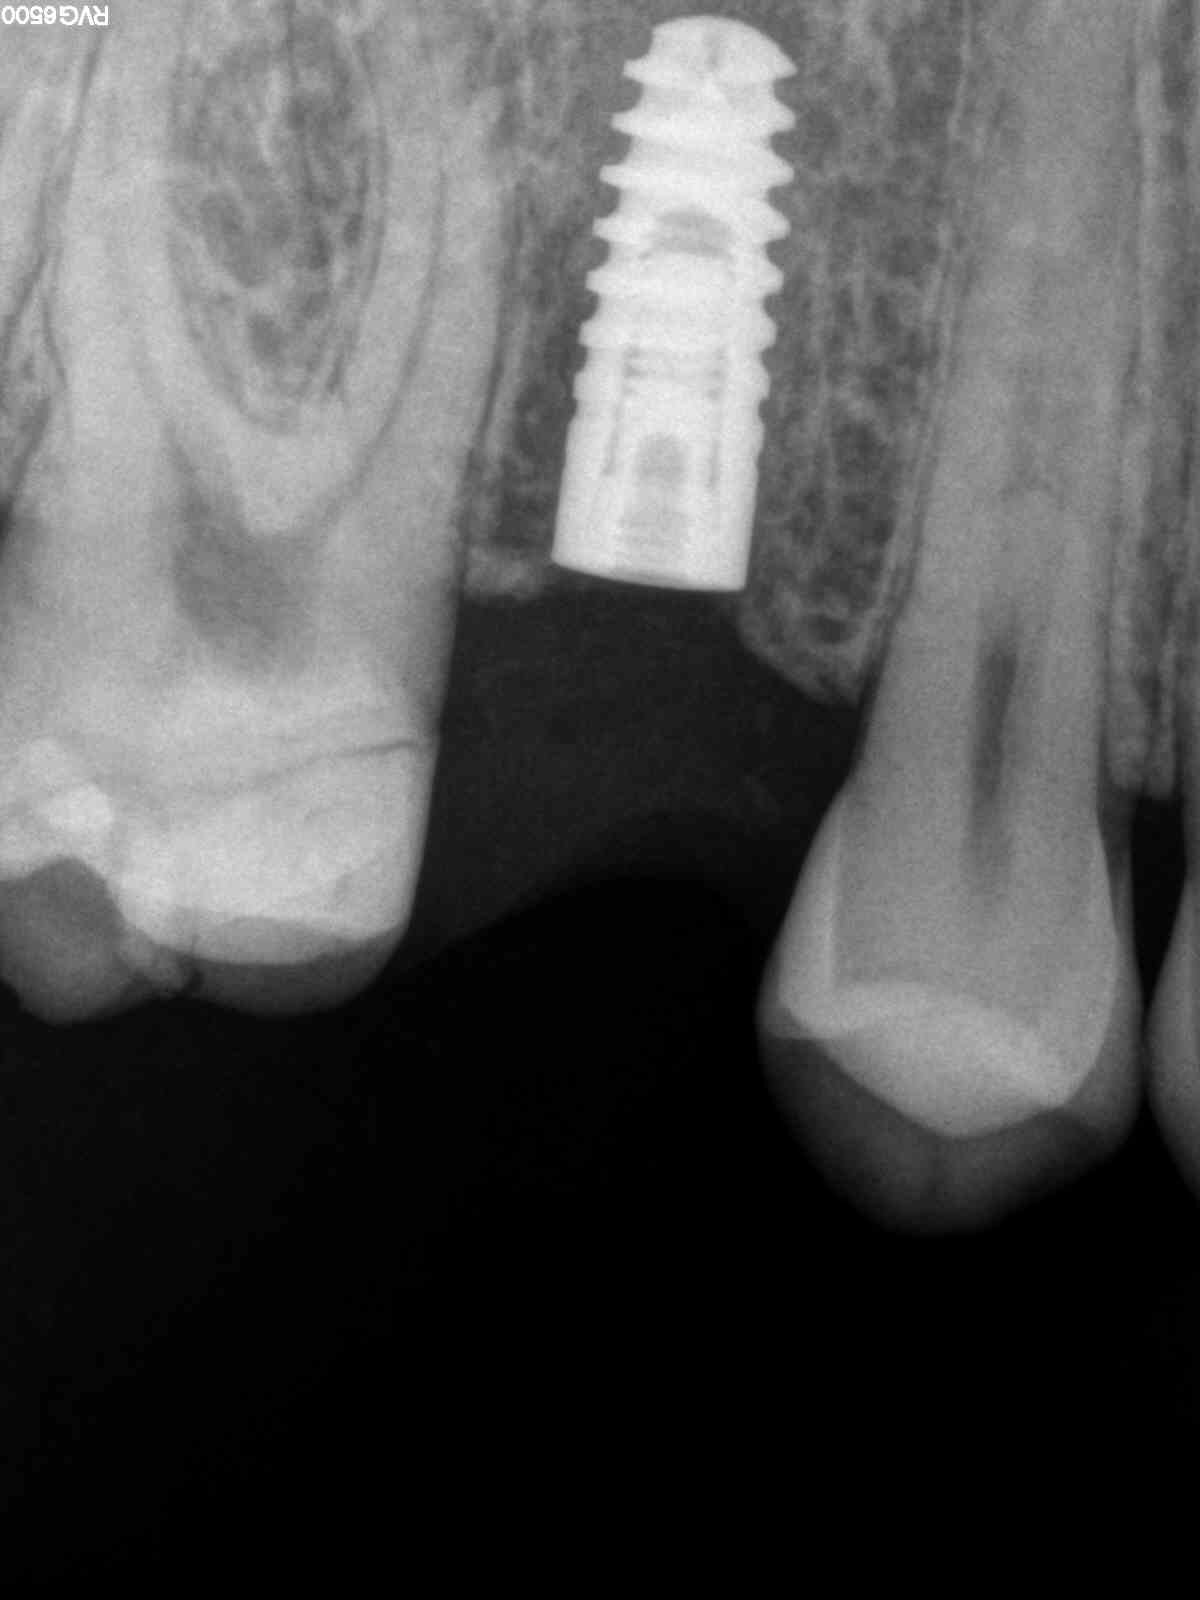

He received his Diploma in Implantology in 2016 from the University of Pretoria, which he passed with Distinction. He is also a member of the International Team for Implantology (ITI), which is based in Switzerland and offers members access to the latest research and cutting-edge techniques.